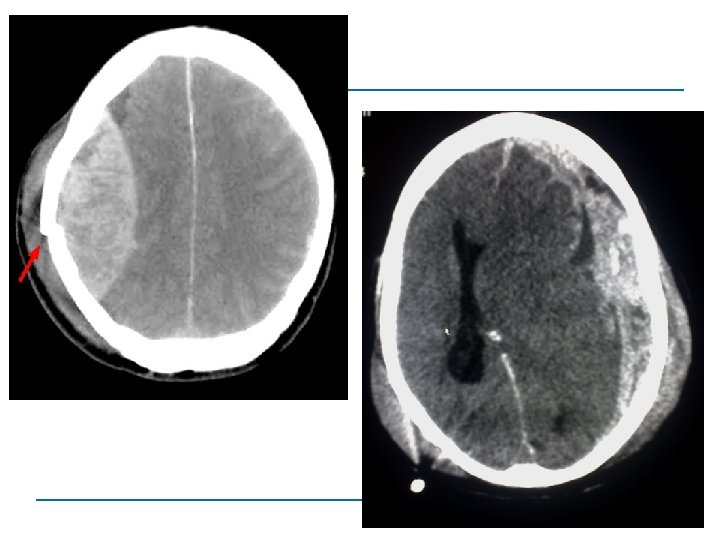

Vermeidung sekundäre Hirnverletzung! RR und pa. O 2 normal RR normal und pa. O 2 < 60 mm. Hg RR < 90 mm. Hg und pa. O 2 normal RR < 90 mm. Hg und pa. O 2 < 60 mm. Hg 27% 33% 60% 75% Chesnut et al. , J Trauma, 1993 Chesnut et al. , Acta Neurochir, Suppl (Wien), 1993 Sicherstellung einer ausreichenden Oxygenierung (A, B) und einer adäquaten Kreislaufsituation (C) entscheidend

GCS (Glasgow Coma Scale) SHT I° SHT III° GCS 13 -15 GCS 9 -12 GCS ≤ 8

Monitoring • CCT • Klinik (Zeichen einer beginnenden Einklemmung)

Take Home Message Neurologische Funktionseinschränkung (D= Disability) Optimierung von Blutdruck und Oxygenierung ABC vermeidet sek. Hirnschäden bei Pupillendifferenz nur notwendigste Basis-Diagnostik